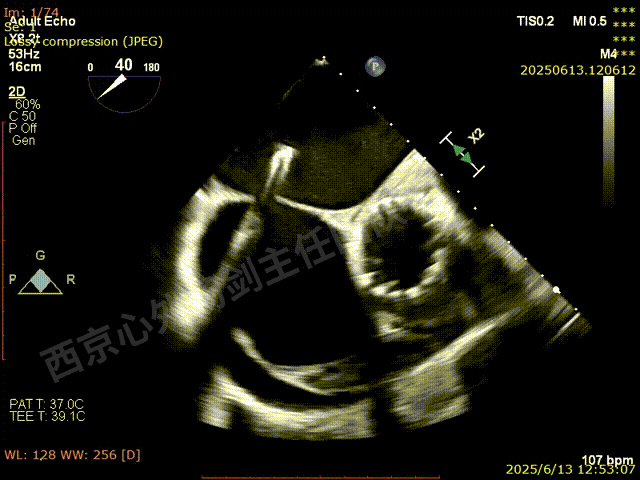

第一枚XTW打开确认orientation,穿刺位置良好无需调整hug

XTW进入瓣下,以较小的角度先捕捞后叶

反复尝试,瓣叶卷曲,前后瓣叶不明确

捕捞完成后确认orientation,gripper down